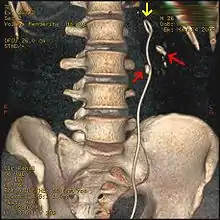

Ureteroscopic surgery

Ureteroscopy has become increasingly popular as flexible and rigid fiberoptic ureteroscopes have become smaller. One ureteroscopic technique involves the placement of a ureteral stent (a small tube extending from the bladder, up the ureter and into the kidney) to provide immediate relief of an obstructed kidney. Stent placement can be useful for saving a kidney at risk for postrenal acute kidney failure due to the increased hydrostatic pressure, swelling and infection (pyelonephritis and pyonephrosis) caused by an obstructing stone. Ureteral stents vary in length from 24 to 30 cm (9.4 to 11.8 in) and most have a shape commonly referred to as a "double-J" or "double pigtail", because of the curl at both ends. They are designed to allow urine to flow past an obstruction in the ureter. They may be retained in the ureter for days to weeks as infections resolve and as stones are dissolved or fragmented by ESWL or by some other treatment. The stents dilate the ureters, which can facilitate instrumentation, and they also provide a clear landmark to aid in the visualization of the ureters and any associated stones on radiographic examinations. The presence of indwelling ureteral stents may cause minimal to moderate discomfort, frequency or urgency incontinence, and infection, which in general resolves on removal. Most ureteral stents can be removed cystoscopically during an office visit under topical anesthesia after resolution of urolithiasis.[114] Research is currently uncertain if placing a temporary stent during ureteroscopy leads to different outcomes than not placing a stent in terms of number of hospital visits for post operative problems, short or long term pain, need for narcotic pain medication, risk of UTI, need for a repeat procedure or narrowing of the ureter from scarring.[115]